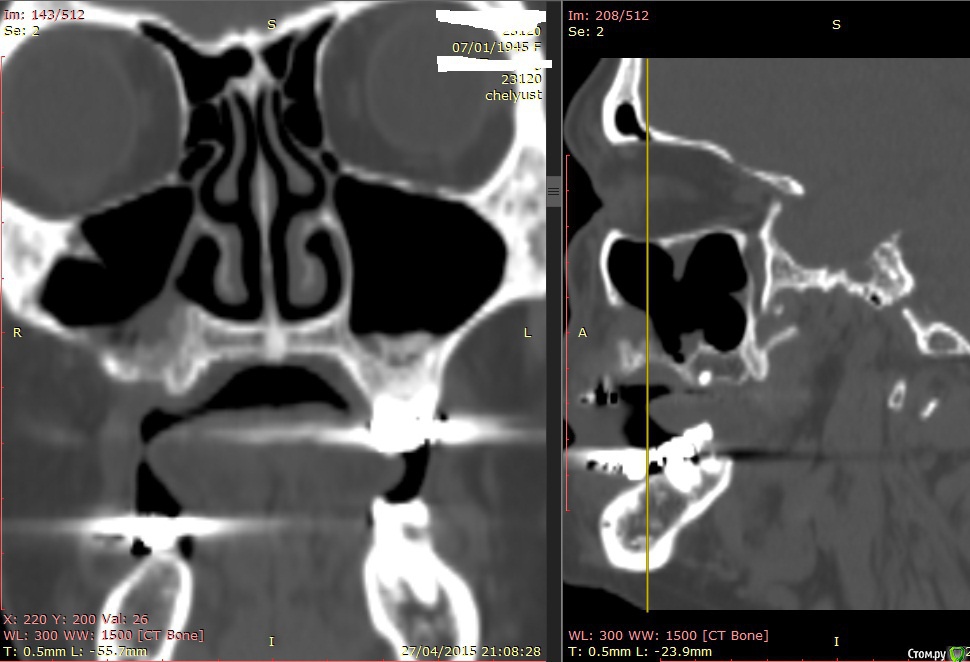

Alexey Doc Опубликовано 29 апреля, 2015 Поделиться Опубликовано 29 апреля, 2015 В клинику с целью протезирования обратилась пациентка 70 лет.Ортопед направил на консультацию. В анамнезе: со слов больной год назад удален зуб 1.6 после чего сформировался оро-антральный свищ. В январе 2015 года выполнена правосторонняя радикальная гайморотомия с удалением 1.5, 1.7 зубов. Сопутствующая патология в стадии компенсации.На сегоднещний день жалоб кроме отсутствия зубов нет.В полости рта : верхний свод преддверия справа плавно перетекает в небо мощным тяжем подвижной слизистой шириной примерно 15-17 мм . Альвеолярный отросток отсутствует. Какой\ие минимально инвазивные( учитывая возраст пациентки) способы аугментации вы бы применили у этой больной для последующего протезирования с опорой на имплантатах? Буду рад любому мнению и рац.предложению.Ниже свежие срезы КТ. Ссылка на комментарий

zzkz Опубликовано 29 апреля, 2015 Поделиться Опубликовано 29 апреля, 2015 Фото бы во рту еще.Не вижу естественного соустья. Если нет, опять к лору. То что искусственно сделали работать в должной мере не будет, нарушение дренажа приведет к проблемам. Мерцательный эпителий(кажется так называется) работает от природы в сторону естественного соустья.Еще есть гипертрофия слизистой.А так если слизистая пазухи и слизистая полости рта "одно целое" аккуратно сепарировать и мембрану с тит.усилением. Мобилизовать извините дохера надо. Потом слизистую щеки на место возвращать. Ссылка на комментарий

АнтонТЛТ Опубликовано 29 апреля, 2015 Поделиться Опубликовано 29 апреля, 2015 Фото бы во рту еще.Не вижу естественного соустья.на первом срезе 1 Ссылка на комментарий